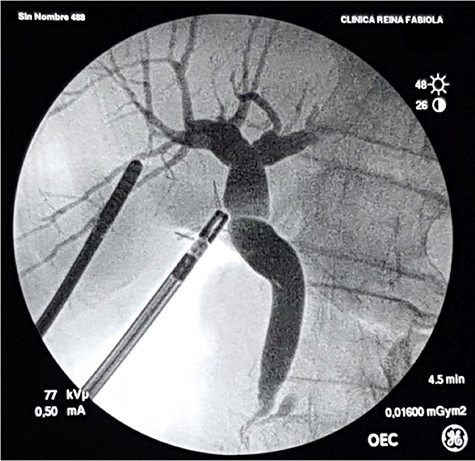

With the patient in supine position, the trocars were placed as per the American technique of LC. After releasing lax adhesions, the remaining cystic duct was recognized and individualized from the CBD with cold scissors. Once isolated, a lateral incision in the cystic stump was made for CBD exploration (Fig. 3). Under radiological guidance, the clip was successfully removed through the cystic duct with endoscopic hose-type biopsy forceps (Fig. 4). A control cholangiography confirmed CBD clearance (Fig. 5). At the end of the procedure, the metallic clip was removed from the abdominal cavity (Fig. 6), and the remnant cystic stump was secured with a PDS Endoloop Ligature in order to avoid any future migration (Video 1 shows our technique). The patient recovered uneventfully and was discharged 3 days after surgery.

Control intraoperative cholangiography using a 5-Fr catheter and an Olsen clamp demonstrates free flow of contrast into the duodenum without defects or stenosis.